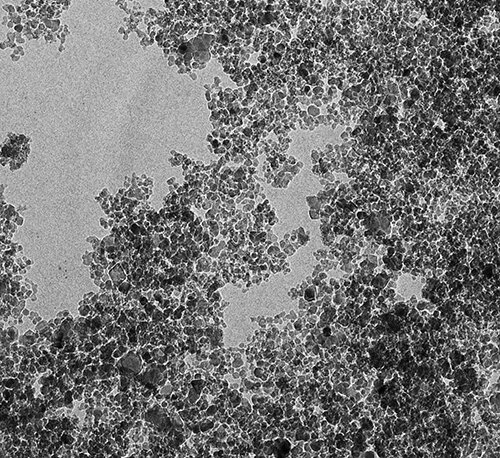

— Любой обычный лекарственный препарат действует не только на место локализации заболевания, но и на весь организм в целом, оказывая на него токсическое воздействие. Мы ищем пути снижения токсичности и дозировки лекарств и возможности сделать их действие более направленным, — объяснил ученый. Было необходимо найти специальные транспортировщики, которые доставляли бы препарат прямо к пораженным клеткам, минуя здоровые. С течением времени решение нашлось: наночастицы. На данный момент существует около 400 видов наночастиц, которые создают из различных материалов. Ученые обратили особое внимание на детонационные наноалмазы благодаря уникальному набору их химических и биологических свойств. Особенно важно, что наноалмазы нетоксичны и биосовместимы с организмом. Наноалмаз состоит из частиц атомов углерода, собранных в алмазную решетку. Частицы имеют размер около пяти нанометров, а их поверхность насыщена функциональными (химическими) группами, с помощью которых можно прикреплять лекарственные вещества к поверхности частиц наноалмаза. Главным открытием в процессе исследованийстал тот факт, что при прикреплении к частицами наноалмаза лекарственного вещества последнее в ряде случаев не только усиливает свое терапевтическое действие, но и приобретает новые фармакологические эффекты, ранее неизвестные для нативного (неприкрепленного) лекарственного вещества. Так, известный препарат «Глицин» при создании системы его доставки с наноалмазом обнаружил совершенно новые, неизвестные ранее фармакологические эффекты. Самым значимым из них является снижение смертности при инсульте и тяжести побочных эффектов в постинсультном периоде. В один день нами было подано восемь патентных заявок на новые эффекты «наноглицина». Также ведется активный поиск новых усиленных фармакологических эффектов других веществ при их прикреплении к наноалмазу. Например, мы пытаемся разработать системы доставки лекарственных веществ против таких социально значимых заболеваний, как туберкулез и отложение солей пирофосфата кальция (псевдоподагра).